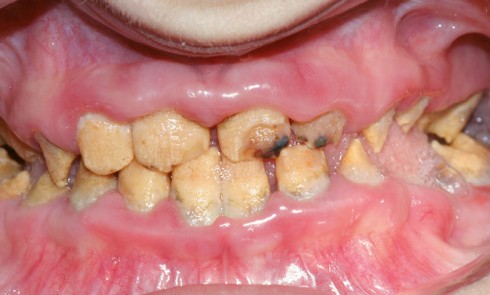

Amélogenèse imparfaite

L’amélogenèse imparfaite (AI) est l’expression d’altérations génétiques associées à des mutations de nombreux gènes codant pour les protéines de l’émail...

L’amélogenèse imparfaite, nom donné à un groupe hétérogène de pathologies affectant le développement de l’émail des deux dentures, a pour...

Définition L’amélogenèse imparfaite est le nom donné à un groupe hétérogène de pathologies caractérisées par un défaut inné du développement...

Une pathologie est dite rare lorsqu’elle affecte moins d’un individu sur 2 000 dans une population. Les amélogenèses imparfaites héréditaires (AIH)...